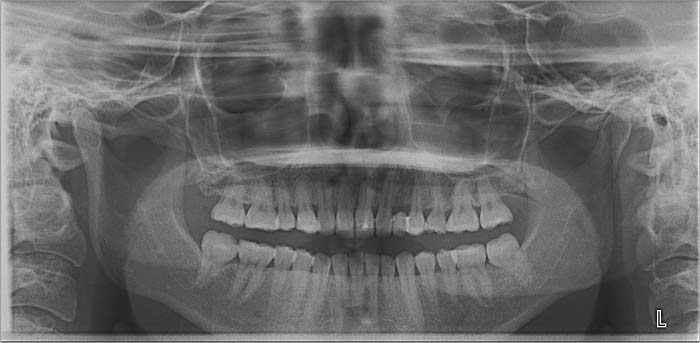

初診日 2023年10月12日

2024年 10月 下顎MTM開始